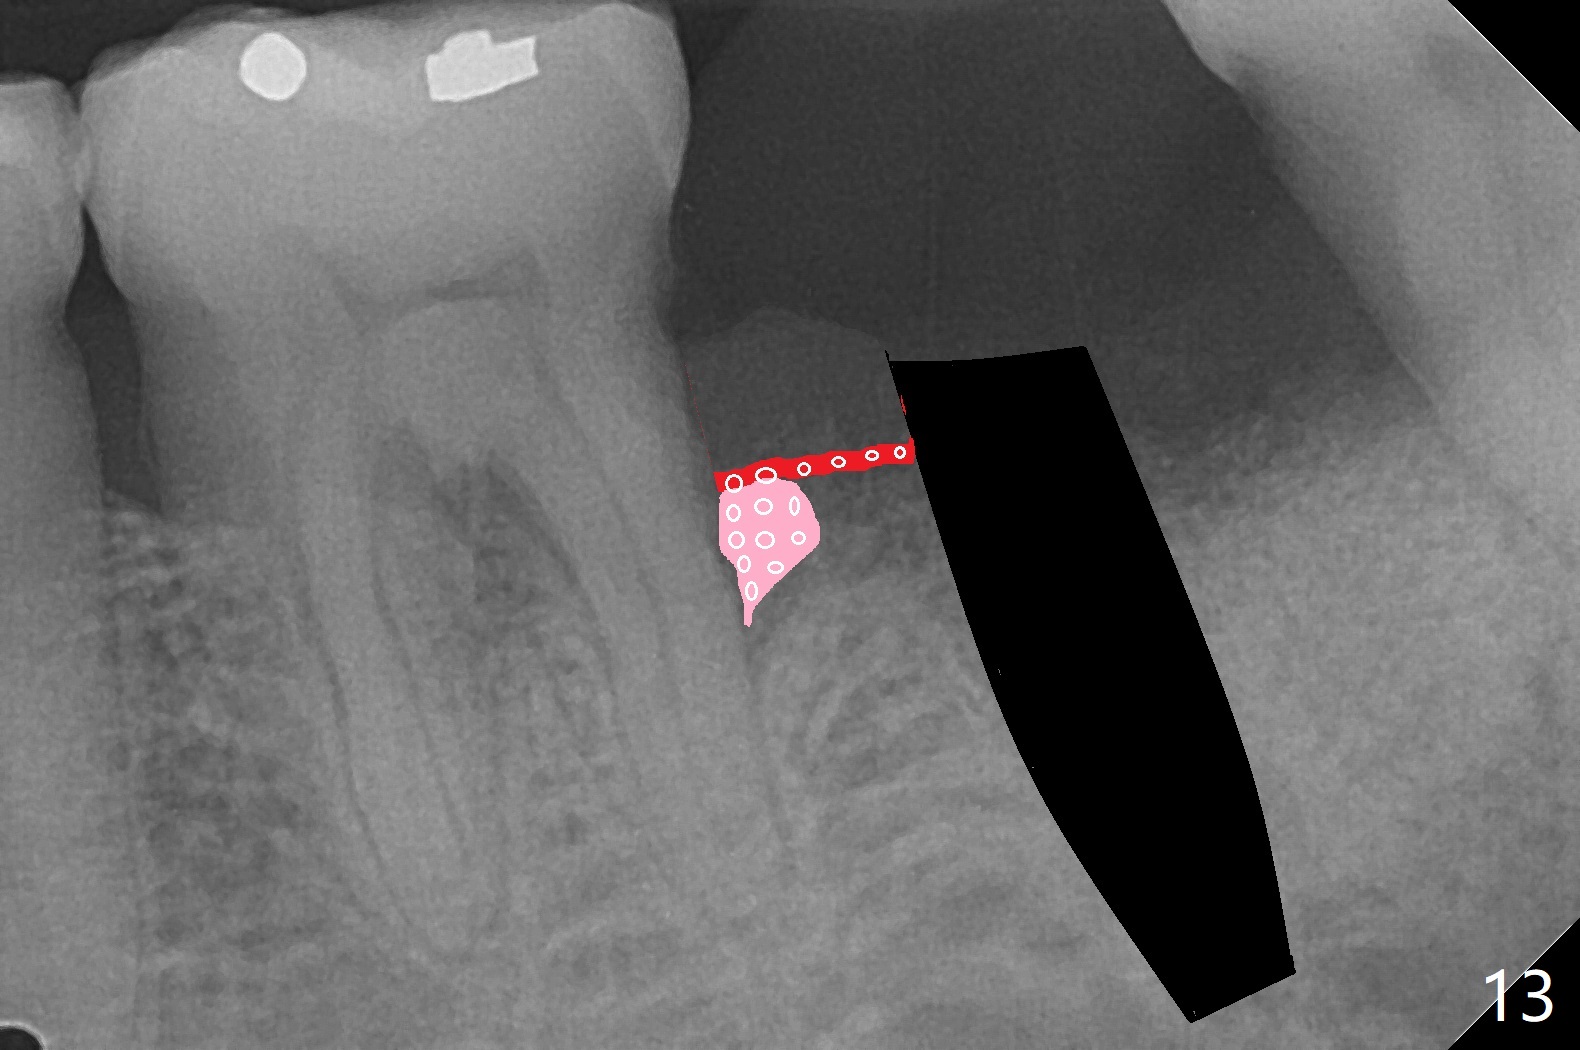

完成钻洞后(图十),潜行分离(掀开)近中牙龈(图十一),去除6远中肉芽组织和结石(图十二),涂Endogain,放置粘性骨粉(图十三),最后放置植体。